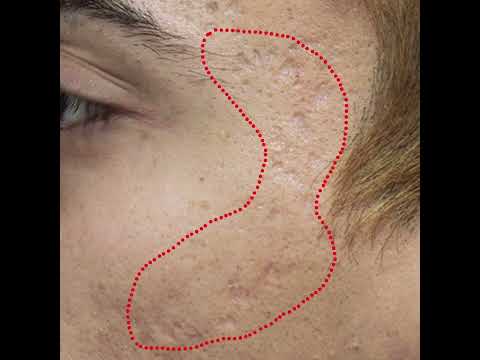

Microneedling plus TCA 15% peel for Acne Scars #Shorts

This video serves to educate and give information about anything related to skin and skincare and shall in no way take the place of a proper consultation with an expert, such as a board-certified dermatologist.

Microneedling plus TCA 15% peel for Acne Scars #Shorts